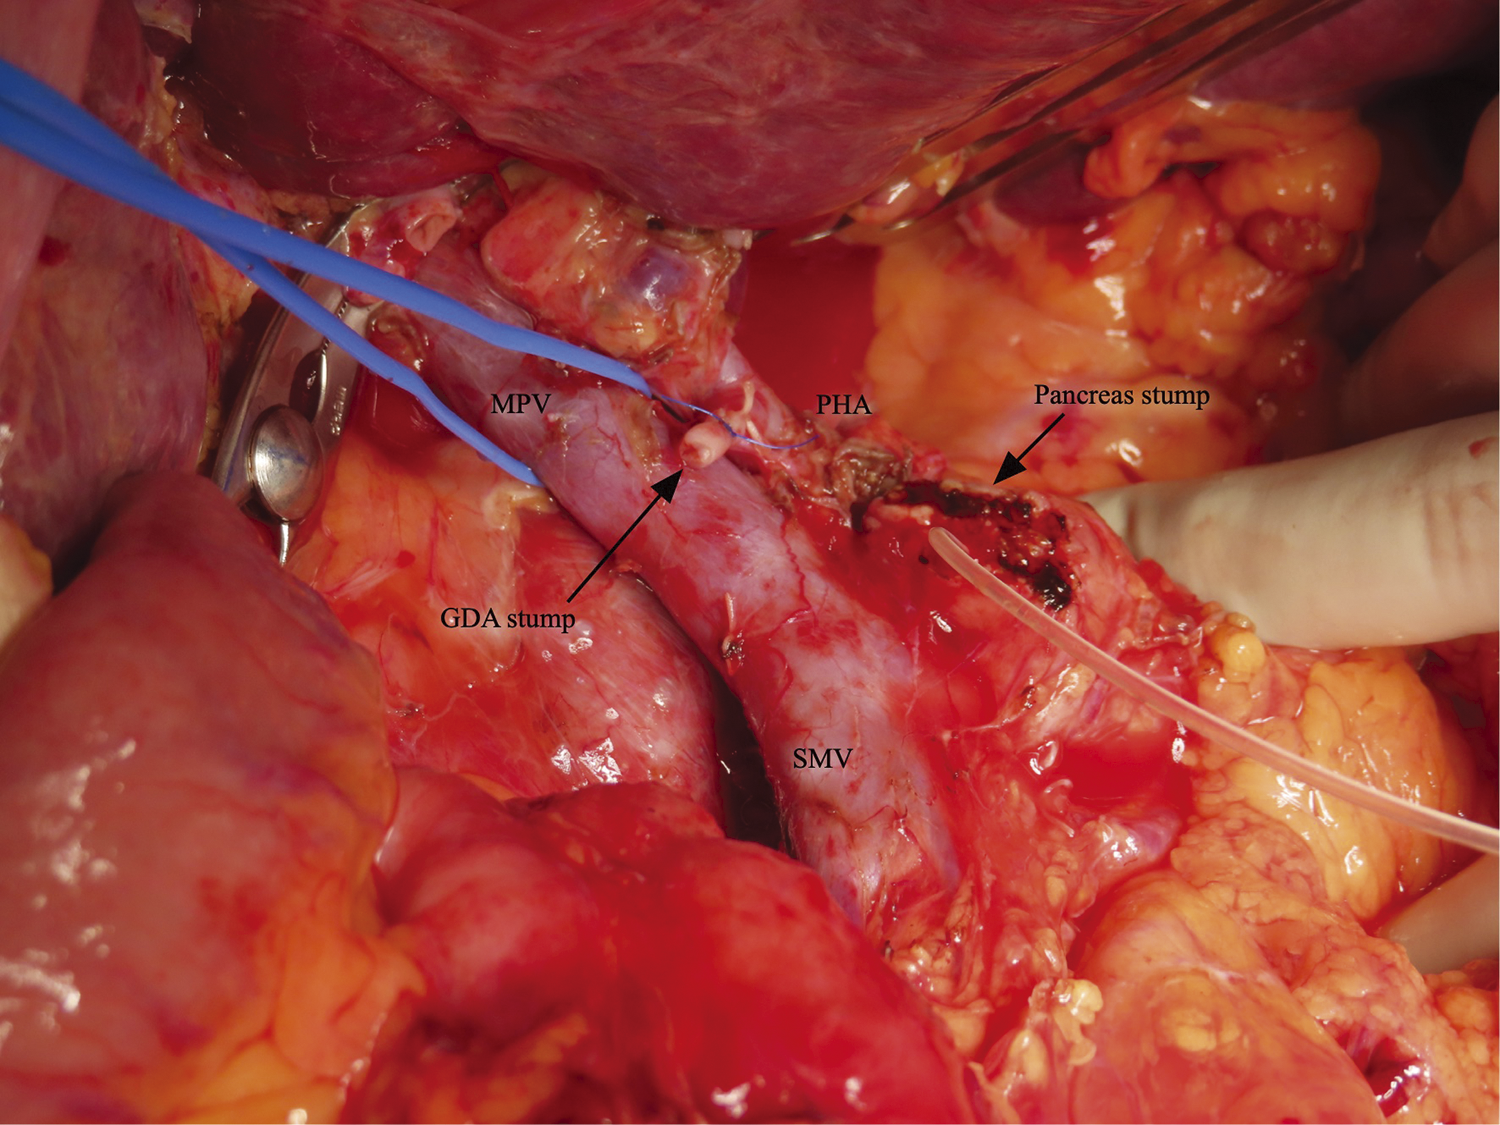

A 53-year-old Southeast Asian man presented to a local physician with abdominal pain. He had no specific previous medical history or prior treatments. Abdominal ultrasonography revealed hepatomegaly. Since his abdominal pain was resistant to any medication, he was referred to our hospital for a comprehensive examination and subsequent treatment. Upper gastrointestinal endoscopy revealed an ulcer in the duodenal bulb (Fig. 1), although he had been taking a histamine H2 antagonist. Helicobacter pylori infection was not detected in any examinations. Plain abdominal computed tomography (CT) revealed intrahepatic reticulated calcification (Fig. 2A), indicating the presence of Schistosomiasis japonica. Contrast-enhanced CT demonstrated early enhancement of the pancreatic head and superior mesenteric vein in the late arterial phase (Fig. 2B). Maximum intensity projection (MIP) images revealed blood flow from the gastroduodenal artery (GDA) and superior mesenteric artery (SMA) to tortuous vessels, subsequently draining into the portal venous circulation (Fig. 2C). Based on these results, we diagnosed the patient with pancreatic AVM. His abdominal pain persisted despite treatment with oral acetaminophen and proton pump inhibitors. Continuous intravenous fentanyl injection relieved his abdominal pain. However, the duodenal ulcer did not improve upon the second upper gastrointestinal endoscopic examination. We considered that the duodenal ulcer was likely caused by the abnormal peri-pancreatic circulation due to the pancreatic AVM, and surgical resection of the pancreatic head was needed to alleviate his symptoms. Considering the risk of increased intraoperative blood loss due to abundant arterial blood flow caused by the presence of the AVM in the pancreatic head, preoperative arterial embolization was scheduled for the day before surgery. Angiography revealed the existence of the AVM in the pancreatic head, which was supplied by the GDA and anterior/posterior pancreaticoduodenal artery (AIPDA/PIPDA) branching from the SMA (Figs. 3A and 3B). After selective arterial embolization of the GDA, APIDA, and PIPDA using gelatin sponges (Serescue; Nippon Kayaku, Tokyo, Japan), AVM was no longer visible under angiography of the celiac axis or SMA (Figs. 3C and 3D). We did not use coils because we were concerned that intra-arterial coils might hamper arterial ligation and division. No complications occurred after arterial embolization until the next day. Since there were no abnormal laboratory data just before surgery, SSPPD was performed. After laparotomy, GDA and peripancreatic arterial branches from SMA were firstly divided to reduce the pancreatic blood flow. The intraoperative findings did not demonstrate any impact of arterial embolization on the pancreatic parenchyma (Fig. 4). The operation time was 453 min, and the blood loss was 336g. The patient was discharged on the 16th postoperative day with no complications and has not experienced abdominal pain since.

Surgical resection and arterial embolization have been reported as treatment modalities for pancreatic AVMs. Although arterial embolization is a minimally invasive procedure, it is difficult to embolize all AVM-associated arteries. When conservative treatment and arterial embolization are ineffective, surgical resection should be considered. However, excessive intraoperative blood loss due to abundant peri-pancreatic arterial flow is a serious hazard. In the literature, 2 studies reported that intraoperative blood loss during pancreaticoduodenectomy for AVM in the pancreatic head without arterial embolization was 1260 and 1950g, respectively.9,10) Additionally, 2 reports described the effectiveness of preoperative arterial embolization in reducing the intraoperative blood loss during resection of AVM in the pancreatic head. Intraoperative blood loss during pancreaticoduodenectomy for AVM in the pancreatic head with preoperative arterial embolization of the GDA alone was 605g in 1 report,11) and another report did not describe the blood loss.12) In contrast to the 2 reports, we almost completely embolized AVM-related arteries via GDA, AIPDA, and PIPDA. After complete embolization, we considered the risks of arterial embolization, such as pancreatic necrosis or pancreatitis due to arterial ischemia.13) To avoid such risks associated with ischemia, we scheduled surgery for the day after arterial embolization. Fortunately, our patient did not show any complications related with arterial embolization until the next morning following embolization. As a result, SSPPD was safely performed, and the intraoperative blood loss was 336g. Thus, we strongly believe that the preoperative arterial embolization is safe and effective in reducing the intraoperative blood loss during resection of pancreatic AVMs. Moreover, we addressed the responsible arteries first to minimize the risk of massive bleeding as much as possible because the artery-first approach could reduce the intraoperative blood loss.14,15) Based on these points, we recommend planned arterial embolization before resection of pancreatic AVMs.